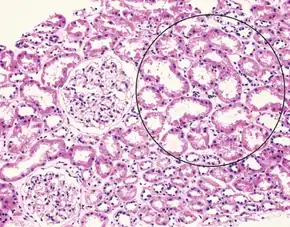

| Liver histology is altered in HRS while kidney histology is normal. The upper image is a trichrome stain (chicken wire appearance) of cirrhosis of the liver, the most common cause of HRS. | |